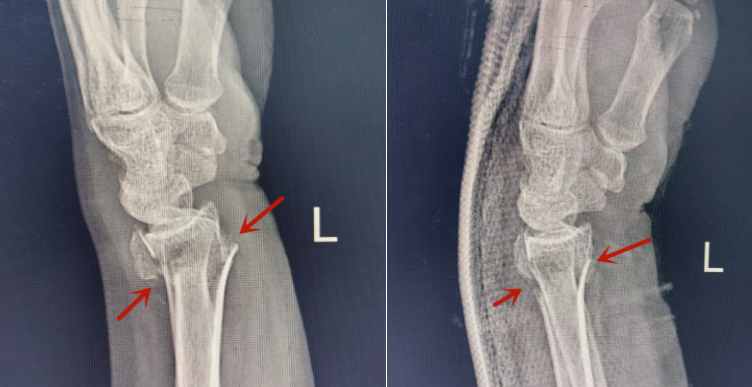

医院急诊医学科接诊后,通过询问病史及体查,考虑手腕骨折,遂立即给患者安排手腕照片检查,结果显示桡骨远端骨折,伴有明显移位。通过局部麻醉,精准手法复位及石膏外固定后,患者疼痛得到缓解,骨折复位效果满意。

左:骨折复位前;右图:手法复位后